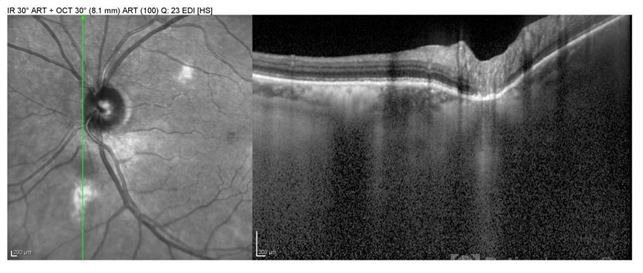

- choroidal nevus

- Optical coherence tomography system

- OCT image of the small choroidal nevus just inferior to the disc showing no elevation or subretinal fluid.